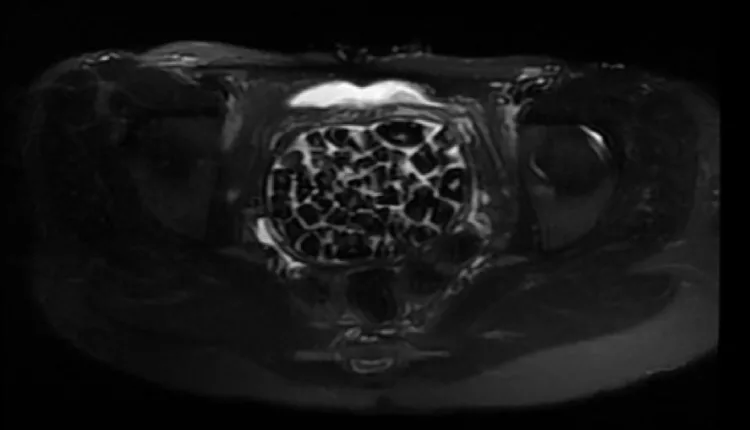

Turkish Doctors Remove 287 Stones From Young Woman

In Türkiye, 21-year-old Fatma Nur Öztürk underwent surgery after severe abdominal pain revealed a rare condition. Doctors discovered and removed 287 stones, the largest measuring 2.5 centimeters, from her bladder and vaginal area.

The medical team described the case as extremely rare in medical literature. Öztürk said the pain had been unbearable but added, “I feel very good now” after the operation.